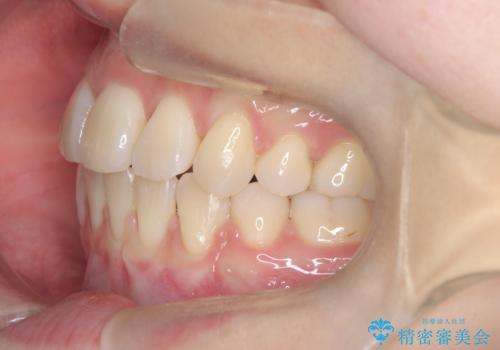

- 患者様は下顎の前歯が3本しかないという特異な歯列を持ち、噛み合わせのバランスが崩れていました。上下の歯の本数が通常と異なるため、抜歯部位の選定が重要となるケースでした。診査の結果、歯の位置や咬合のバランスを考慮し、上顎の両側小臼歯2本と左下の小臼歯1本を抜歯することで、上下の噛み合わせを整える方針としました。矯正装置は、**目立ちにくいハーフリンガル(上顎は裏側矯正・下顎は表側矯正)**を採用しました。

まず、計画通りに抜歯を行い、歯列のスペースを確保しました。上顎は裏側矯正(リンガル)で目立たないように配慮しながら歯を後方へ移動し、下顎は表側矯正を使用して、3本の前歯の位置関係を調整。上下の歯の噛み合わせを細かくコントロールしながら、全体のバランスを整えました。治療後は「歯並びがきれいになり、噛み合わせもしっかり合うようになった」と患者様にも満足していただけました。